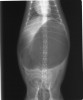

●胃捻転の正式名称は、英語でGastric Dilatation-Volvulusと言い、和訳では胃拡張-

胃軸捻転症である。獣医師間では略してGDVと言う。通常、人や猫では遭遇しない疾患である。

●空気を伴う劇的な胃の拡張があり、急変して来院する。そして、その殆どが捻転を伴っている。90~360度捻転するため、放置すれば、その程度により数時間内で死亡する。

●GDVは急性の、死が切迫した疾患であり、緊急処置を要する。早期の発見と治療開始が救命の基本である。胃拡張は胃の膨張のためであり、通常は嚥下した空気と胃内容物で充満される。胃拡張は胃軸捻転によって悪化する場合がある。

●GDVは胃がその長軸で捻転した時に起こり、これが胃からの流出の完全な閉塞をもたらす。同時に起こる胃-食道吻合部(噴門)の閉塞は嘔吐やおくびによる胃内のガスや内容物(胃内液体)の蓄積減少を不可能にする。

●症状は鼓腸を伴う腹囲膨満で、急性に発症する。嘔気を催すが、ガスや内容物の嘔吐を伴わない。その他に流涎、落ち着かない、呼吸困難などの症状がある。